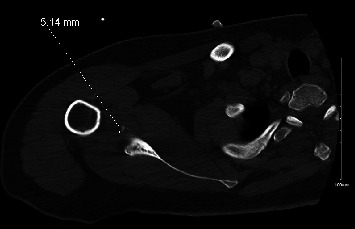

Dislocation of the glenohumeral joint secondary to generalized tonic-clonic seizures is well documented in the medical literature, with posterior dislocation being most commonly described. Still, these occurrences tend to be rare and affect a minority of patients, and fractures associated with dislocations after seizures are even less common. As such, the management of these injuries tends to be quite varied, and there is a paucity of documented cases in the literature. Here, we would like to present two rare cases of anterior shoulder dislocation secondary to seizures, with one patient also sustaining a fracture of the proximal humerus. We would also like to discuss the management and outcomes that have been achieved, since these cases tend to occur in a small number of epileptic patients.